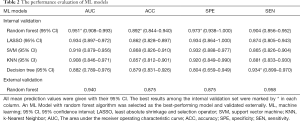

In the internal validation, the mean AUCs of the five ML algorithms were 0.882–0.951 (95% CI: 0.789–0.993), with mean accuracies of 0.857–0.892 (95% CI: 0.812–0.940), mean sensitivities of 0.865–0.934 (95% CI: 0.805–0.970), and mean specificities of 0.804–0.973 (95% CI: 0.659–1.000). Among these ML algorithms, RF achieved the best performance. The mean AUC of RF was 0.951 (95% CI: 0.908–0.993), with a mean accuracy of 0.892 (95% CI: 0.844–0.940), a mean sensitivity of 0.904 (95% CI: 0.856–0.952), and a mean specificity of 0.973 (95% CI: 0.938–1.000). The performance metrics of the ML algorithms are shown in Table 2, and the comparison among ROC curves is presented in Figure 3A.

Full table

In the external validation, the AUC obtained by the RF algorithm was 0.940, with an accuracy of 0.875, a sensitivity of 0.875, and a specificity of 0.958 (Table 2 and Figure 3B). Furthermore, our best-performing model (i.e., RF algorithm) identified BASE as the most critical parameter for the accurate prediction of postoperative IMH status (Figure 4). To better illustrate the importance of BASE, binary logistic regression analysis was derived for prediction of IMH status using BASE in internal validation set. The ROC curve of BASE was showed in Figure 5, with an AUC of 0.911.